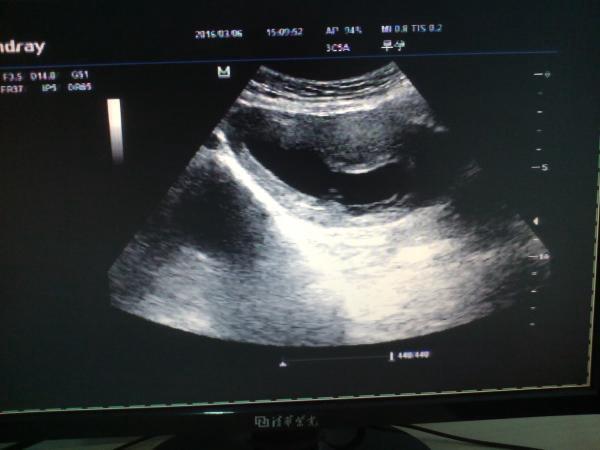

不完全性葡萄胎

病人,女42y,停经有三月余,主诉有断断续续出血为黑色,***检查,孕囊平均经大小约42mm,内见胚芽长约25mm,未见心血管搏动,图如下 CDFI:后壁见丰富得血流信号,胎盘?